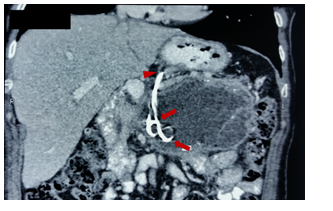

A 62-year-old woman with a history of cholelithiasis and acute biliary pancreatitis managed in a private clinic (severity not specified). She comes 7 months later for abdominal pain and obstructive symptoms (episodes of nausea and post - prandial vomiting). Abdominal palpation revealed pain in epigastrium. Laboratory results: alkaline phosphatase: 422 IU / L. MRCP: walled-off necrosis of 14 x 12 cm in the pancreatic body and tail. EUS: hypoechoic lesion of 10 x 8.3 cm with a solid content of 30 - 40%. Under fluoroscopic and endoscopic guidance, it was punctured with a 19G needle and 2 double Pigtail stents were left. Due to extensive bleeding in the stomach by puncture of vessels in the gastric wall, the patient underwent an urgent exploratory laparotomy and transfixing points at the site of puncture. No perforation was evident. He had a favorable evolution and was discharged (Figures 11&12).

Figure 11 MRCP (T2 weighted image). Delimited lesion in the pancreatic body and tail with solid (arrows) and cystic contents (asterisk).

Figure 12 Contrast-enhanced CT with radiological artifacts at third postoperative day shows mild ascites (arrows).